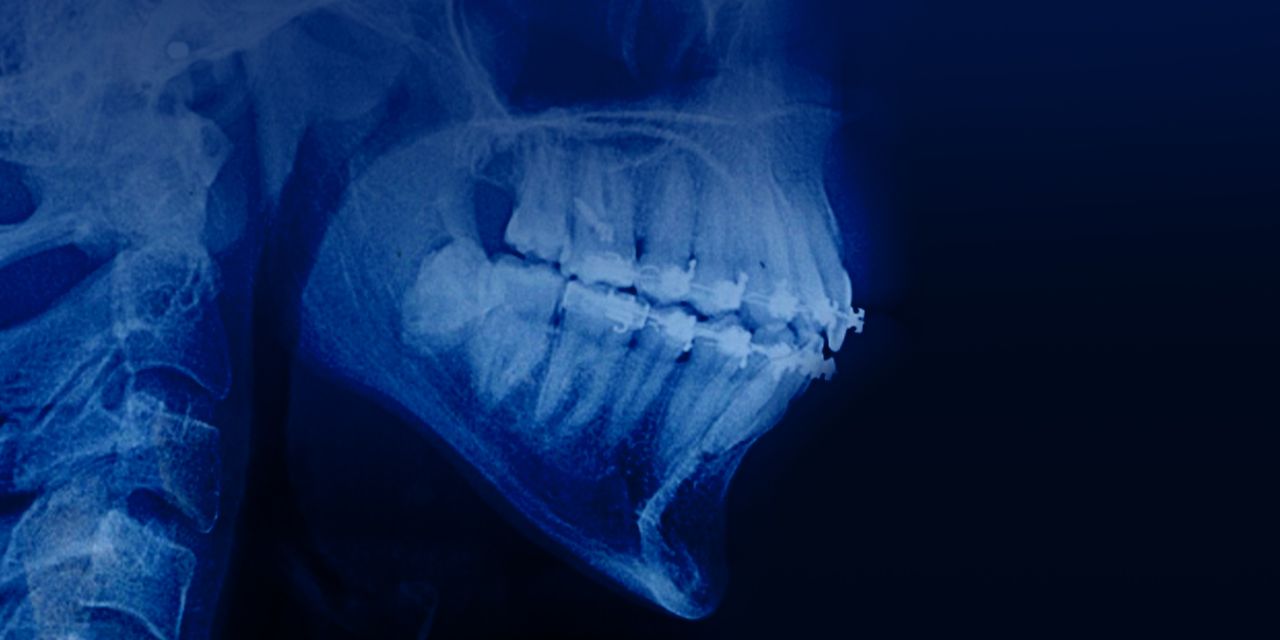

Ортодонтия у пациентов с патологией пародонта и костной ткани

Онлайн-курс по ортодонтическому лечению пациентов с патологией пародонта и костной ткани.